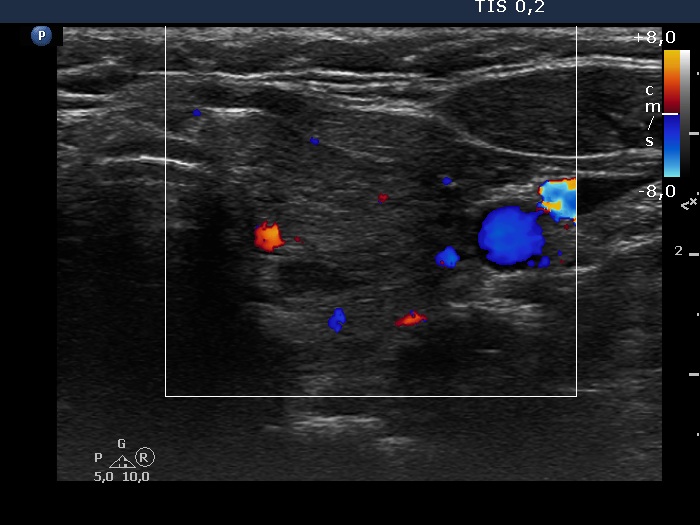

Consecutive patients with the final diagnosis of Hashimoto's thyroiditis - case 51 (1170) (ultrasonographic picture 8)

Left lobe, transverse scan, color Doppler mode. The vascularization is average.